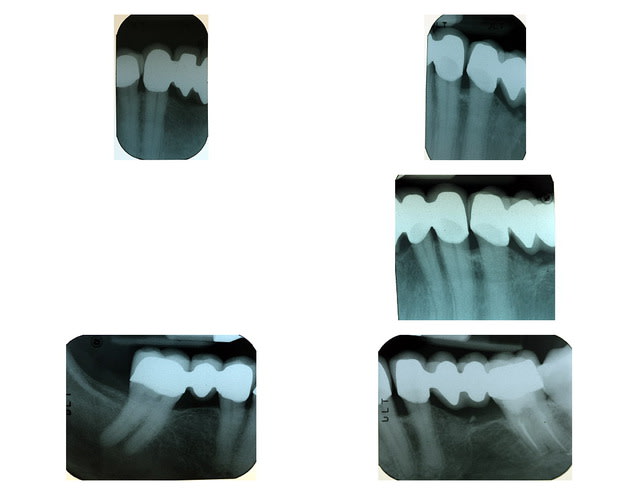

Ci-joint radio des bridge Zircone

Radio zirconia q5smv5 - Eugenol